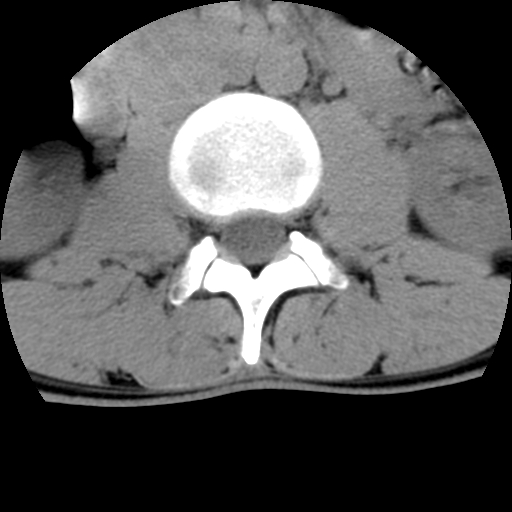

标题: CT16890:男,腰背痛.

男,腰背痛

本人诊断1tb2包虫,请会诊

1)右侧竖脊肌稍低密度肿块伴钙化(性质待定),不排除肿瘤可能;建议行进一步检查。2)腰椎间盘突出。

1.右侧竖脊肌软组织肿块伴团块状钙化,首先考虑血管瘤可能性大;建议行进一步检查;2。腰椎间盘突出。